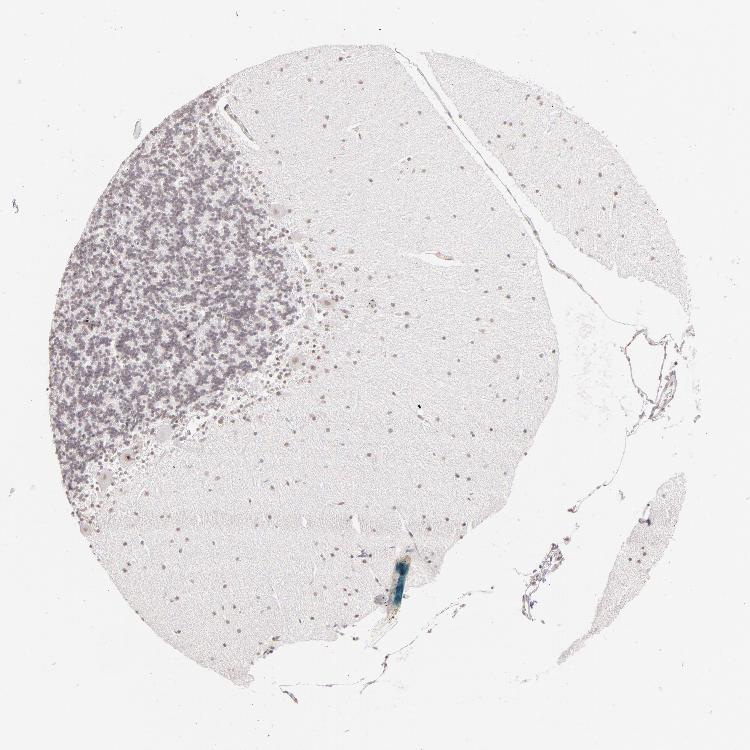

BRAIN CEREBELLUM Show tissue menu

CEREBELLUM - Expression summary

Protein expression

Cerebellumi

On the top, protein expression in current human tissue, based on all annotated cell types, is reported with the units not detected (n), low (l), medium (m) and high (h). Underneath, protein expression in each annotated cell type are reported using the same units.

Protein expression data is based on knowledge-based annotation. For genes where more than one antibody has been used, a collective score is set.

If knowledge-based annotation could not be performed for a gene, no data is displayed here. View antibody staining data further down this page.

Cells in granular layer: Low

Cells in molecular layer: Low

Purkinje cells: Medium

CEREBELLUM - Antibody stainingi

Antibody staining in the annotated cell types in the current human tissue is reported as not detected, low, medium, or high, based on conventional immunohistochemistry profiling in selected tissues. This score is based on the combination of the staining intensity and fraction of stained cells.

Each image is clickable and will lead to virtual microscopy that enables deeper exploration of all samples and also displays staining intensity scores, fraction scores and subcellular localization as well as patient and tissue information for each sample.

Antibody HPA008736Antibody CAB002224Antibody CAB025546

Purkinje cells HighMediumLow

Cells in granular layer MediumNot detectedNot detected

Cells in molecular layer MediumLowLow